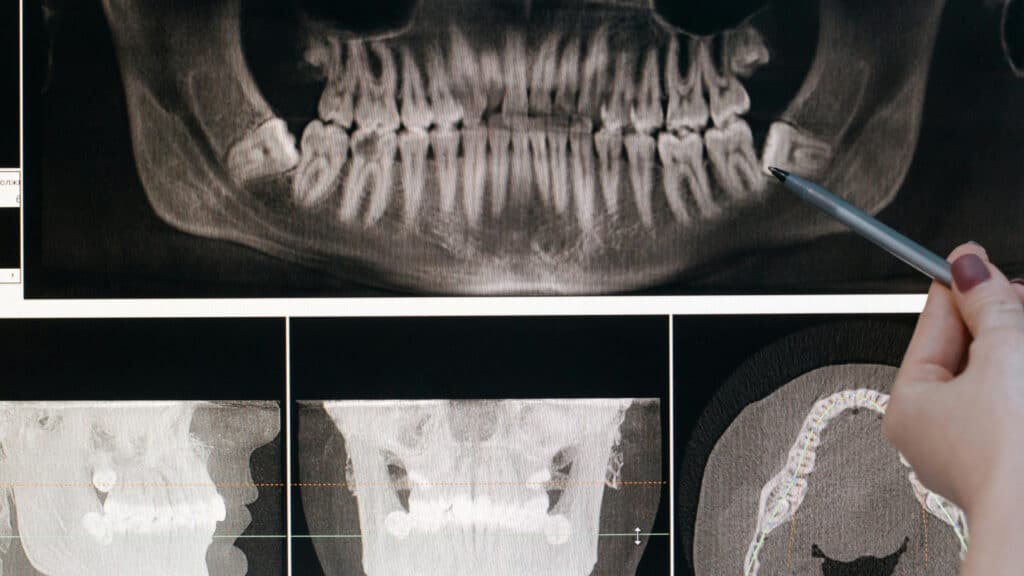

Современные методы диагностики

Самые точные способы:

- КТ/МРТ — лучше всего различают висцеральный и подкожный жир;

- Денситометрия — способна точно определить количество и распределение жира в организме;